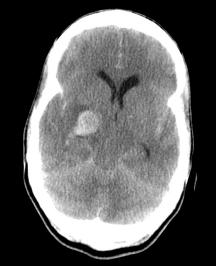

The primary treatment for nonhemorrhagic strokes is the administration of thrombolytics (e.g. tissue plasminogen activator, t-PA) prior to the development of ischemic necrosis. Since thrombolytics would exacerbate hemorrhagic bleeds, the distinction between hemorrhagic and nonhemorrhagic strokes is critical. Fortunately, as you can see, the distinction is quite apparent on a non-contrast CT scan.

Non-contrast CT is a critical component for the evaluation and subsequent treatment of strokes.

When examining these CTs, remember that collections of blood will be radiodense. Initially infarcted brain will show minimal changes on a CT, but after a few days, there is marked effacement of the normal architecture.

Can you distinguish between these CTs and assign them each to one of the aforementioned categories?